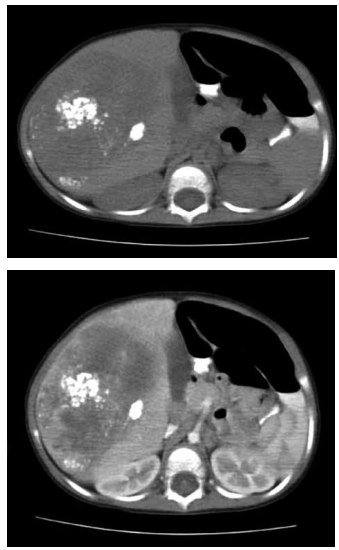

Criança, 18 meses, apresentando massa indolor

palpável no quadrante superior direito do abdome e perda de peso. Solicitados exames laboratoriais demonstrando anemia e elevação de alfafetoproteina (AFP) e

exame de imagem conforme demonstrado abaixo.

A partir do quadro clínico e exame de imagem, pode-se afirmar, EXCETO: